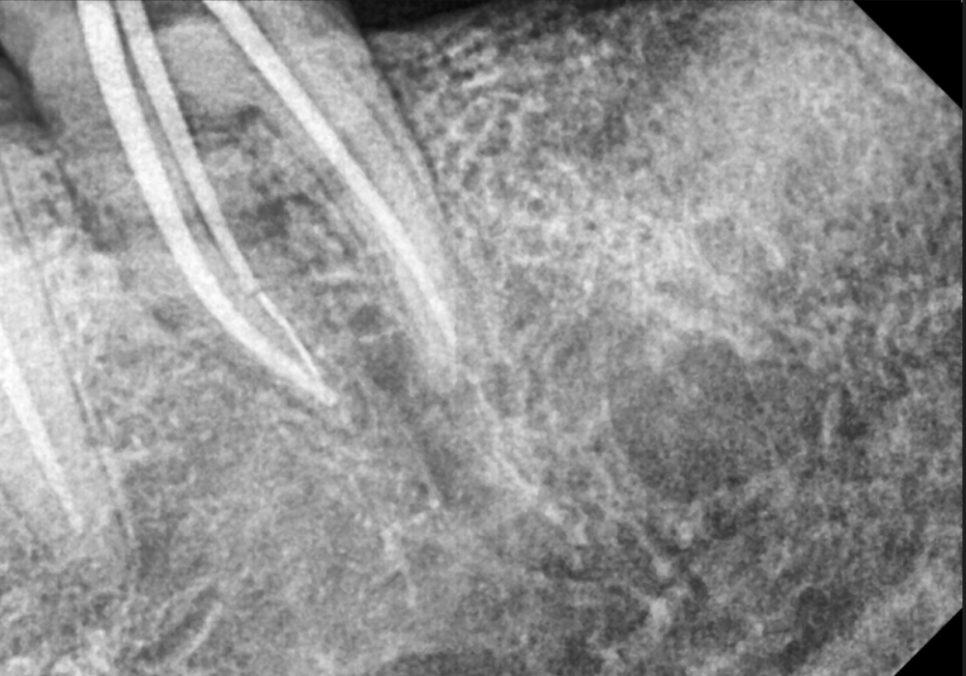

충치가 있긴 했지만

치아 뿌리는 튼튼했기에,

치아 내부의 오염된 신경관을

청소하는 신경치료를 진행했습니다.

251010

오염된 신경을 4번에 걸쳐

꼼꼼히 제거하고 소독한 뒤,

이번에는 구멍이 잘 나지 않는

단단한 재료인 '지르코니아'로 씌워,

튼튼하게 마무리해 드렸습니다.

251103